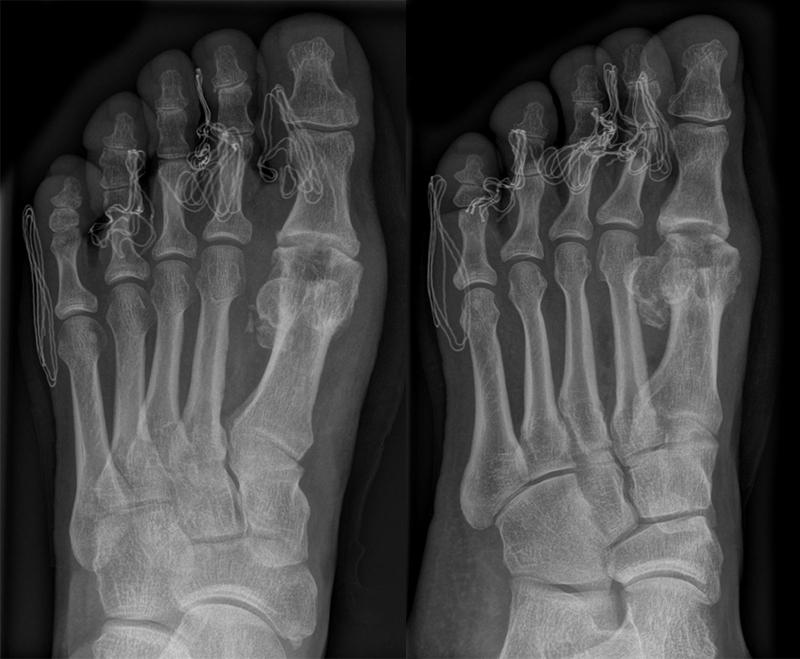

• Röntgen: Fuß belastet in 3 Ebenen.

• Optional MRT und CT bei radiologisch unklaren Verhältnissen.

Zum Lesen der Bildbeschreibung und zur Vollansicht bitte das Bild anklicken (Foto: M. Walther).